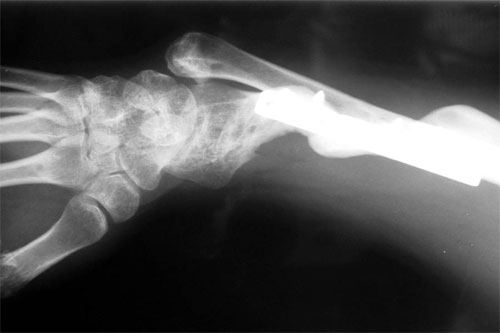

E.R. is a 26 year old male lifeguard who had a severe, unfortunate accident the first time he ever mounted a motorcycle. He was in a coma for many months with head trauma and had fractured his right elbow and forearm at the time of injury. He developed a condition called Heterotopic Ossification which meant that multiple joints “froze-up” due to deposits of calcium in the joint capsules. He was not able to walk until both hips were operated on by an internationally known hip surgeon who then referred him to Dr. Badia to address the stiff Right elbow and deformed forearm. In fact, at the initial visit, the patient stated that he had not moved the right elbow AT ALL for nearly 4 years and was unable to feed or groom himself with that hand. After a series of 3 operations to reconstruct both the elbow and forearm, this young man has gone back to swimming, work and a normal lifestyle.

The pictures depict the application of the dynamic external fixator, which stabilized and provided early motion to the rigid elbow after aggressive release of the capsule and bone excision.